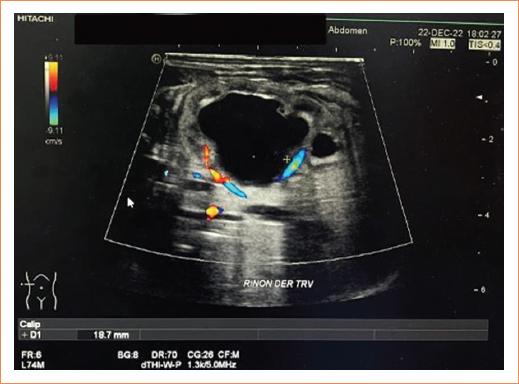

Figura 1 Ultrasonido renal de recién nacido de término de sexo masculino, 5 días de vida extrauterina. Riñón derecho corte transversal: mide 59 x 26 x 35 mm, ectasia de pelvis derecha. Conclusión: hidronefrosis derecha grado IV.

Figura 3 Riñón izquierdo corte transversal, mide 50 x 19 x 25 mm en sus diámetros mayores, ectasia de pelvis izquierda donde alcanza un diámetro de hasta 18 mm. Conclusión: hidronefrosis izquierda grado III.